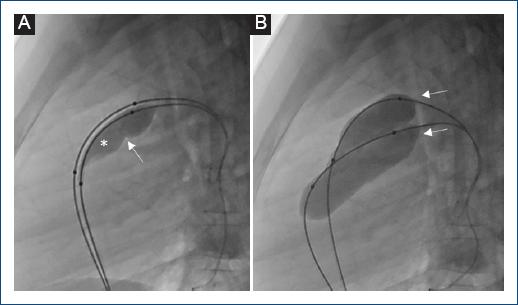

En el laboratorio de hemodinamia, el primer procedimiento se realizó el 19 de mayo de 2022, con un total de 54 cateterismos cardiacos en pacientes menores de 18 años, utilizando el aparato de angiografía Siemens Artis Q. El equipo estuvo conformado por dos médicos cardiólogos pediatras hemodinamistas graduados del Instituto Nacional de Cardiología Ignacio Chávez. Cuarenta y siete de estos con fines terapéuticos y siete con fines diagnósticos (Fig. 1), 37 pacientes fueron de sexo femenino; la edad fue 4.9 ± 4.37 años. El peso 20.6 ± 14.5 kg. La talla fue 100.7 ± 29.2 cm. El tiempo promedio de procedimiento fue 49.3 ± 14.5 min. La cantidad de radiación fue 131.6 ± 249.4 mGy, el medio de contraste utilizado fue 193.7 ± 984 ml. La oclusión del conducto arterioso correspondió a un 46% de los procedimientos, siendo el más frecuente, y el cierre de CIV a un 15%. La valvuloplastia con balón fue del 11% (Fig. 2), aortoplastia con balón en un 9%, cierre de CIA en un 6%, el resto fueron de carácter diagnóstico (Tabla 1). El tiempo de hospitalización fue 19 ± 2 horas.

Figura 2 Secuencia fluoroscópica en proyección lateral izquierda que demuestra valvuloplastia pulmonar con técnica de doble balón en uno de nuestros pacientes. A: se muestran dos balones atravesando la válvula pulmonar, solo uno de ellos iniciando insuflación (*); nótese la formación de una cintura en su cara posterior (flecha) que corresponde al anillo valvular pulmonar. B: se muestra la insuflación total de los dos balones (flechas); nótese la desaparición de la cintura previamente descrita al lograr la dilatación del anillo pulmonar.